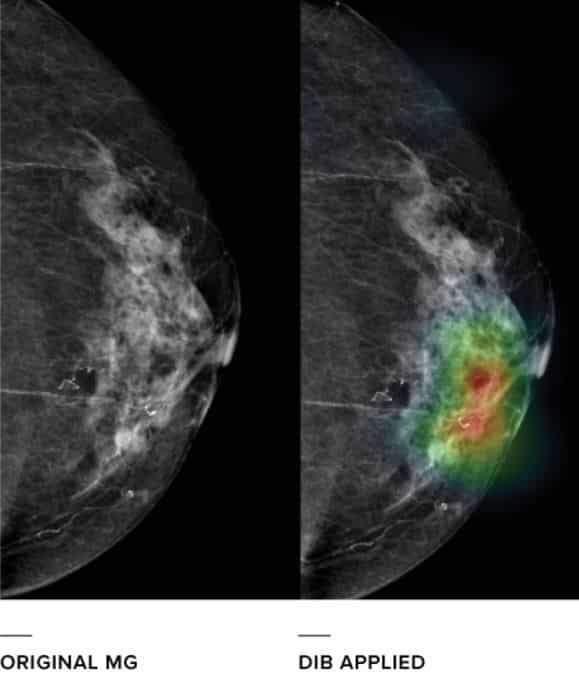

Founded in 2013, Seoul-based startup Lunit has taken in $5.46 million in funding so far from investors that include Softbank (TYO:9984) to develop a “data-driven imaging biomarker” (DIB) technology that helps physicians analyze and interpret medical imaging data. Listed as one of the top 100 AI startups to watch by CB Insights, Lunit was also recognized as one of the top-5 startups for social impact by NVIDIA (NASDAQ:NVDA). They are primarily targeting breast and lung cancer for which 20% of cases are currently missed using screening tests. Here’s an example of what the technology does:

According to an article by Venturebeat, “general practitioners see an improvement in correct diagnoses, going from 80 percent to 83 percent, using Lunit’s technology“.